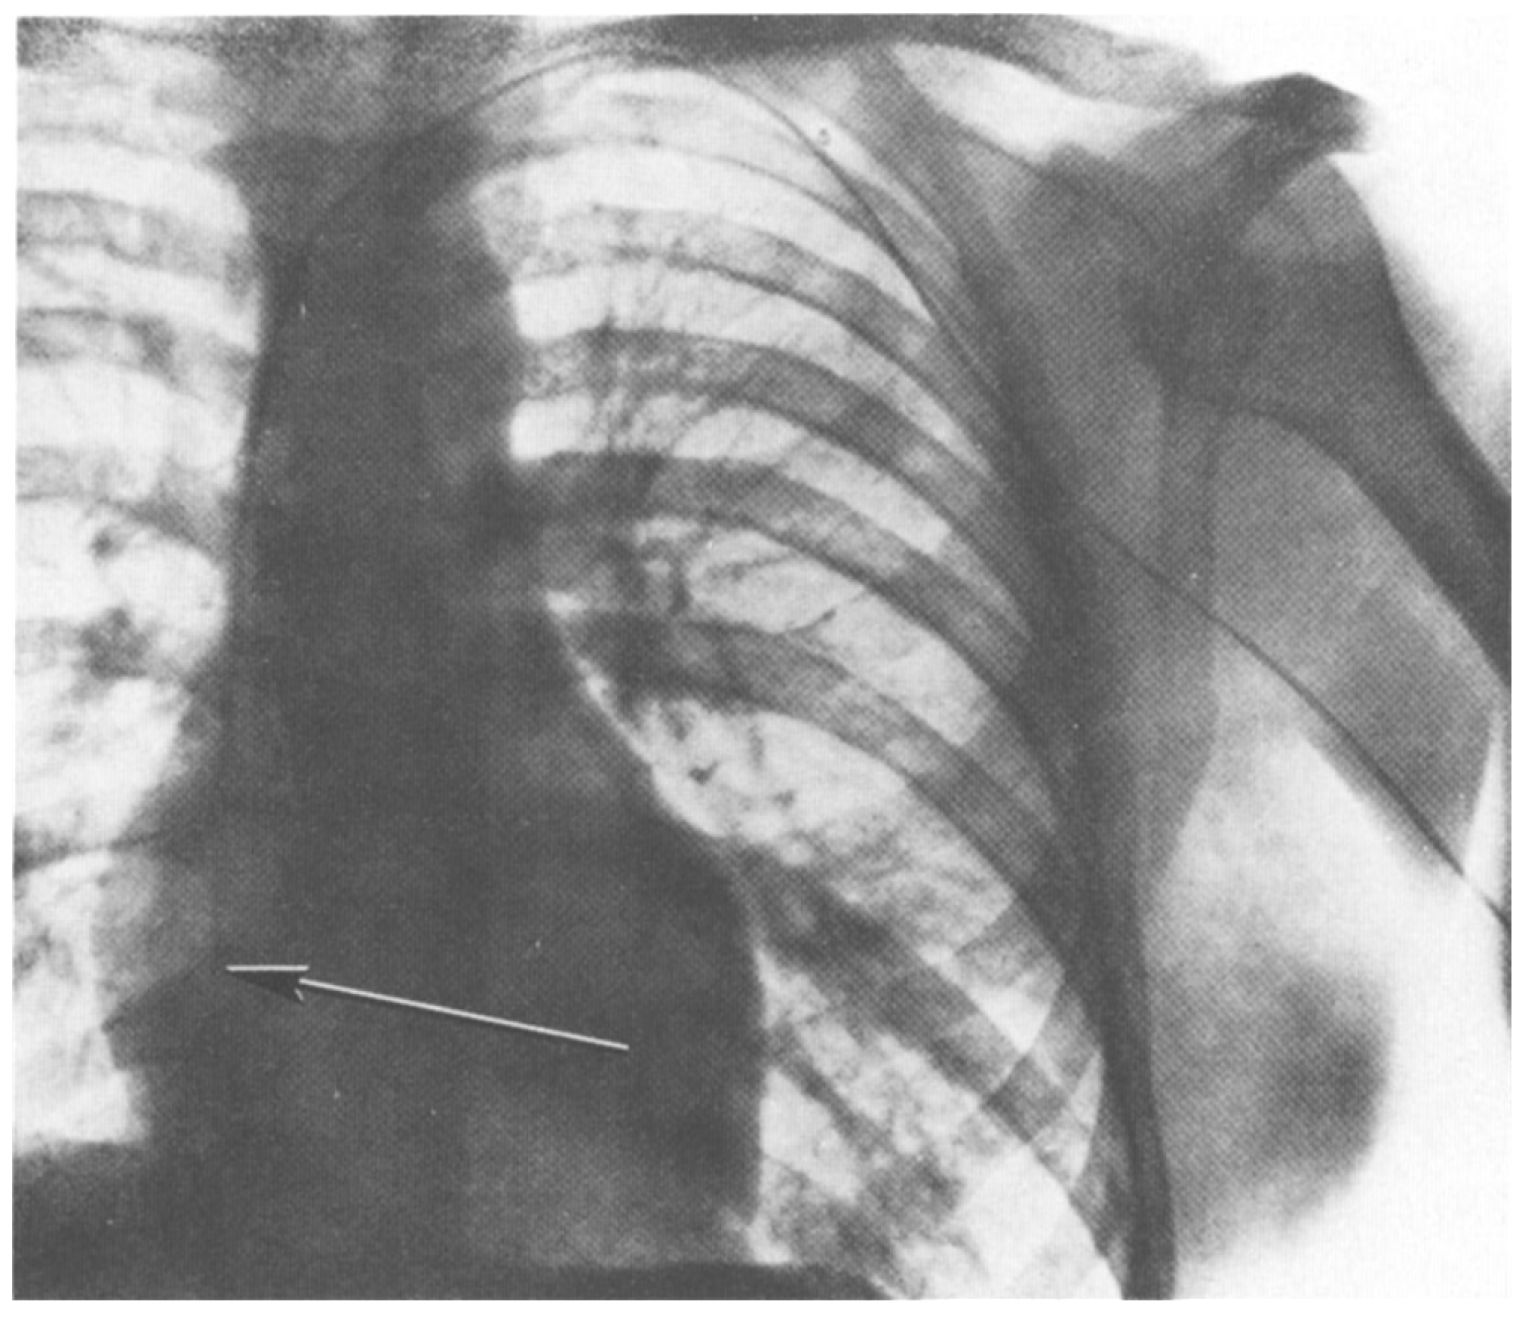

In 1929 at the Auguste-Viktoria Hospital in Eberswalde, Germany, Dr. Werner Forssmann fed a catheter through his arm vein all the way to his heart. He recorded this feat on x-ray (using an x-ray machine one floor above his own lab; see Figure 1). The x-ray shown in Figure 1 documented Forssman’s self-experiment and was published that year (Forssmann, 1929). This daring work, for which Forssmann was eventually awarded the Nobel Prize in Physiology or Medicine, ushered in the field of cardiac catheterization. The story of Forssmann’s experiment is retold in a recent article on overregulation (Morris, 2023) and in greater detail in a book on self-experimentation (Altman, 1998).

X-ray of W. Forssmann’s torso after self-catheterization. Catheter shown on x-ray from original publication (Forssmann, 1929). From the original figure legend, “the catheter passes directly inward from the left arm, under the clavicle at the chest wall, and makes a downward bend at the place of junction with the jugular vein, lying near the margin of the great-vessel shadow and the shadow of the spine, and reaching as far as the right atrium. On another passage, the catheter did not reach any further than this. “I watched carefully for any other effects, or signs of irritation of the cardiac mechanism, but could not identify any. In our institution there is a considerable distance between the operating rooms and the x-ray unit. To go from one to the other I had to climb staircases on foot and return, while the probe was lying within my heart, but I was not aware of any unpleasantness. Passage and removal of the catheter were entirely painless, accompanied only by the above-mentioned sensations. Later on, I could find no sequelae to the procedure…” (Forssmann translated by Meyer, 1990).